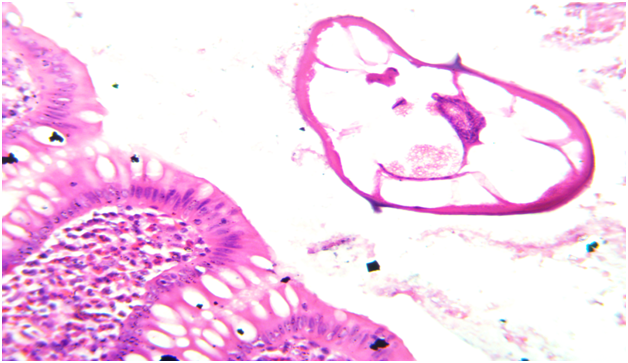

Figure 1 Microscopic photo showing mucosa of appendix with lumen showing multiple enterobious vermicularis parasite. (HE, X10)

Figure 2 Microscopic photo showing mucosa of appendix with eosinophils in lamina propria and enterobious vermicularis parasite in lumen. (HE, X40)